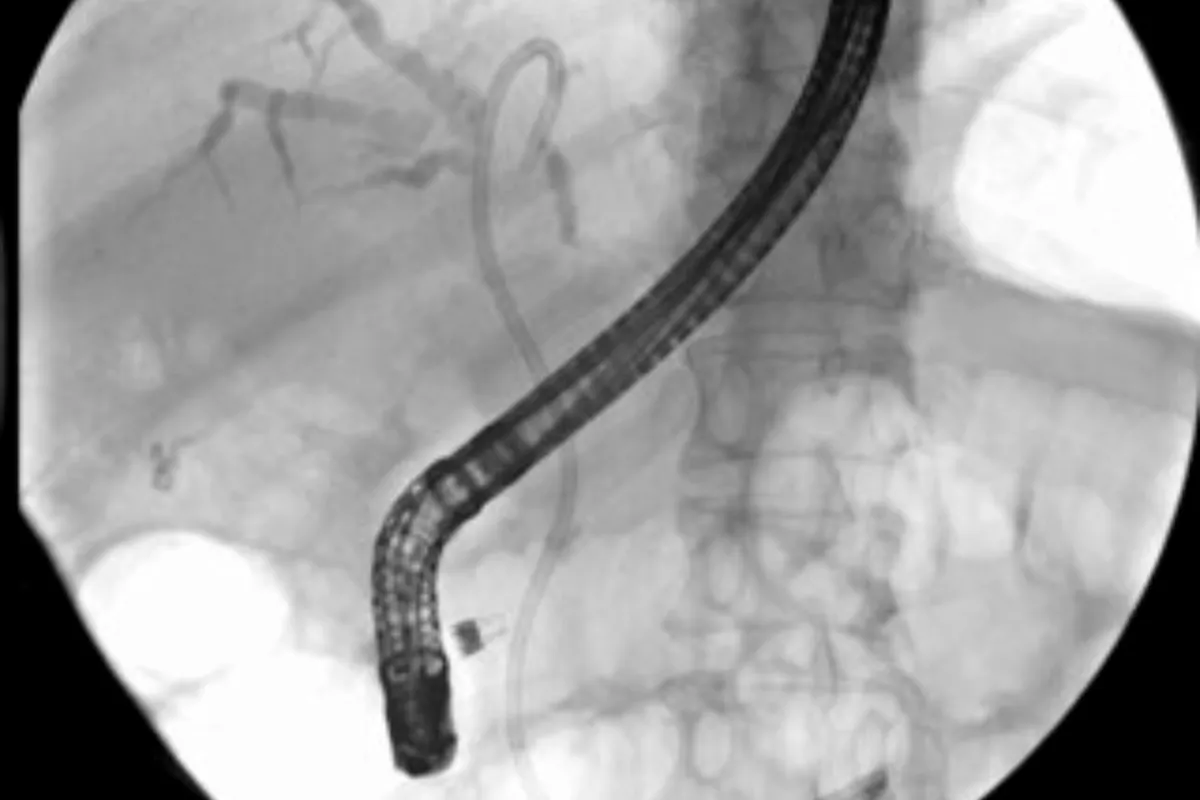

Peripheral Angioplasty procedure at Sarda Vascular Centre Dehradun

Interventional Radiology (IR) uses real-time imaging such as X-ray, ultrasound, CT, or MRI to guide tiny instruments through the body for treatment — without large surgical incisions.